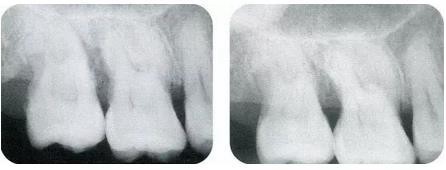

▼圖13-7,8 術(shù)前與術(shù)后8個月的x片。牙槽骨明顯改善。